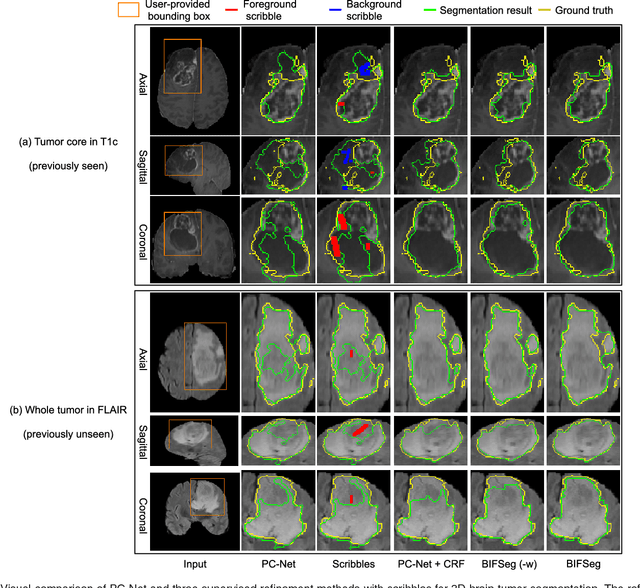

Abstract:Convolutional neural networks (CNNs) have achieved state-of-the-art performance for automatic medical image segmentation. However, they have not demonstrated sufficiently accurate and robust results for clinical use. In addition, they are limited by the lack of image-specific adaptation and the lack of generalizability to previously unseen object classes. To address these problems, we propose a novel deep learning-based framework for interactive segmentation by incorporating CNNs into a bounding box and scribble-based segmentation pipeline. We propose image-specific fine-tuning to make a CNN model adaptive to a specific test image, which can be either unsupervised (without additional user interactions) or supervised (with additional scribbles). We also propose a weighted loss function considering network and interaction-based uncertainty for the fine-tuning. We applied this framework to two applications: 2D segmentation of multiple organs from fetal MR slices, where only two types of these organs were annotated for training; and 3D segmentation of brain tumor core (excluding edema) and whole brain tumor (including edema) from different MR sequences, where only tumor cores in one MR sequence were annotated for training. Experimental results show that 1) our model is more robust to segment previously unseen objects than state-of-the-art CNNs; 2) image-specific fine-tuning with the proposed weighted loss function significantly improves segmentation accuracy; and 3) our method leads to accurate results with fewer user interactions and less user time than traditional interactive segmentation methods.